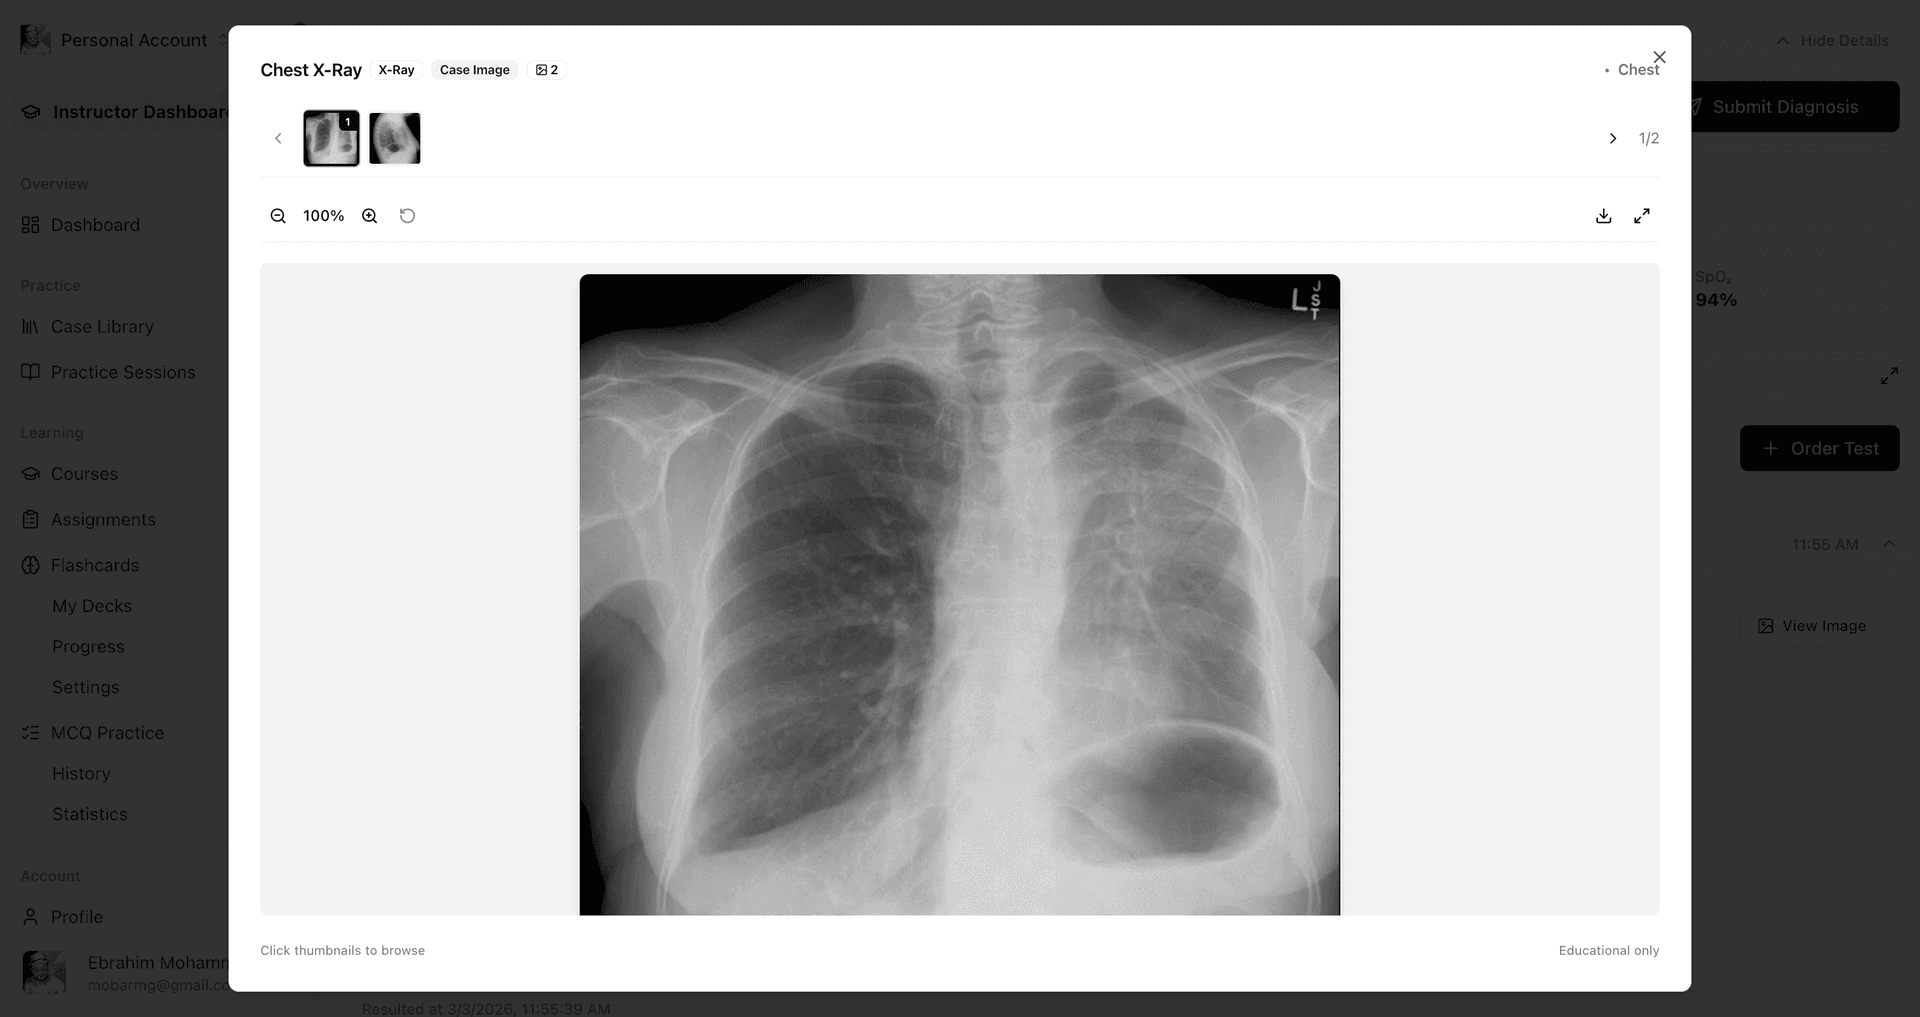

Order diagnostic tests, interpret laboratory results, and analyze medical imaging just like in real clinical practice. Build confidence in diagnostic decision-making with access to authentic lab panels and radiological studies.